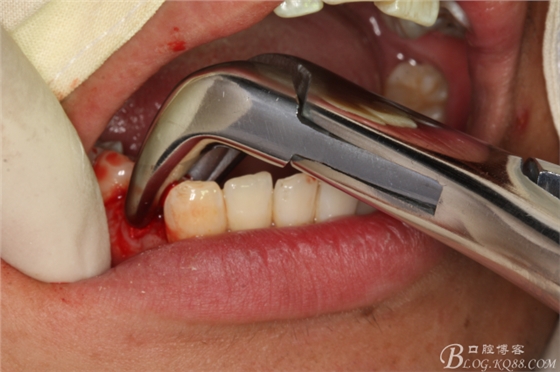

圖20.金剛砂車針片切44牙冠、消除鄰牙阻力

圖21.片切完成的44牙冠

圖22.微創(chuàng)挺增間隙

圖23.放置牙鉗拔除

圖24.拔除44